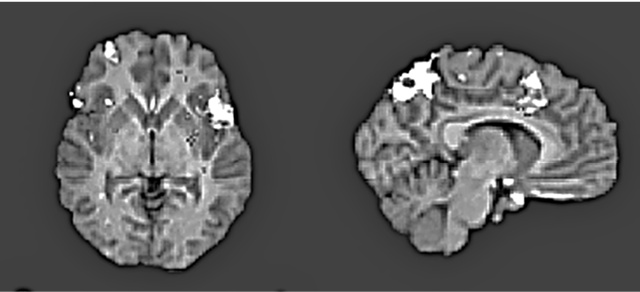

Но это было еще не все. Харрис обнаружил, что оценка «верю» сопровождалась усилением активности в вентромедиальной префронтальной коре (рис. 8.1a ниже) – участке мозга, отвечающем за совмещение факта и эмоции и изменение поведения в ответ на изменение обстоятельств (другими словами, уравновешивание «за» и «против»). «Не верю», в свою очередь, активизировала переднюю островковую долю мозга (рис. 8.1b) – участвующую в том числе и в кодировании негативных реакций, таких как боль и отвращение, и в оценке приятности различных вкусов и ароматов.

Иллюстрация к книге — Флипноз. Искусство мгновенного убеждения [i_052.jpg]

Рис. 8.1a. Усиление активности в вентромедиальной префронтальной коре в ответ на правдивые утверждения («верю»), относящиеся к семи разным тематическим категориям (математика, география, автобиография, религия, этика, семантика и события) (по материалам Харриса и др., 2008)